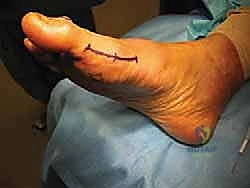

- Positioning: Place the patient in a supine position on the operating table. Crucially, the lower extremity should be naturally externally rotated. This external rotation provides excellent exposure to the medial aspect of the forefoot, which is our surgical field. Ensure the foot is positioned comfortably on a padded pillow or bolster.

Figure 8: Intraoperative view showing the planned incision line and the natural external rotation of the foot, optimizing medial forefoot exposure.

* Tourniquet: We'll apply a well-padded supramalleolar Esmarch tourniquet. This provides a bloodless field, which is absolutely essential for the meticulous dissection required in this area. Ensure the tourniquet time is monitored closely.

Surgical Approach and Incision

The choice of incision is critical to minimize complications and optimize exposure.

- Preferred Incision: We will utilize a longitudinal medial skin incision. This incision is strategically placed slightly plantar to the standard incision used for a bunion excision.

- Incision Length: Typically, a 3-4 cm incision is sufficient, centered over the tibial sesamoid.